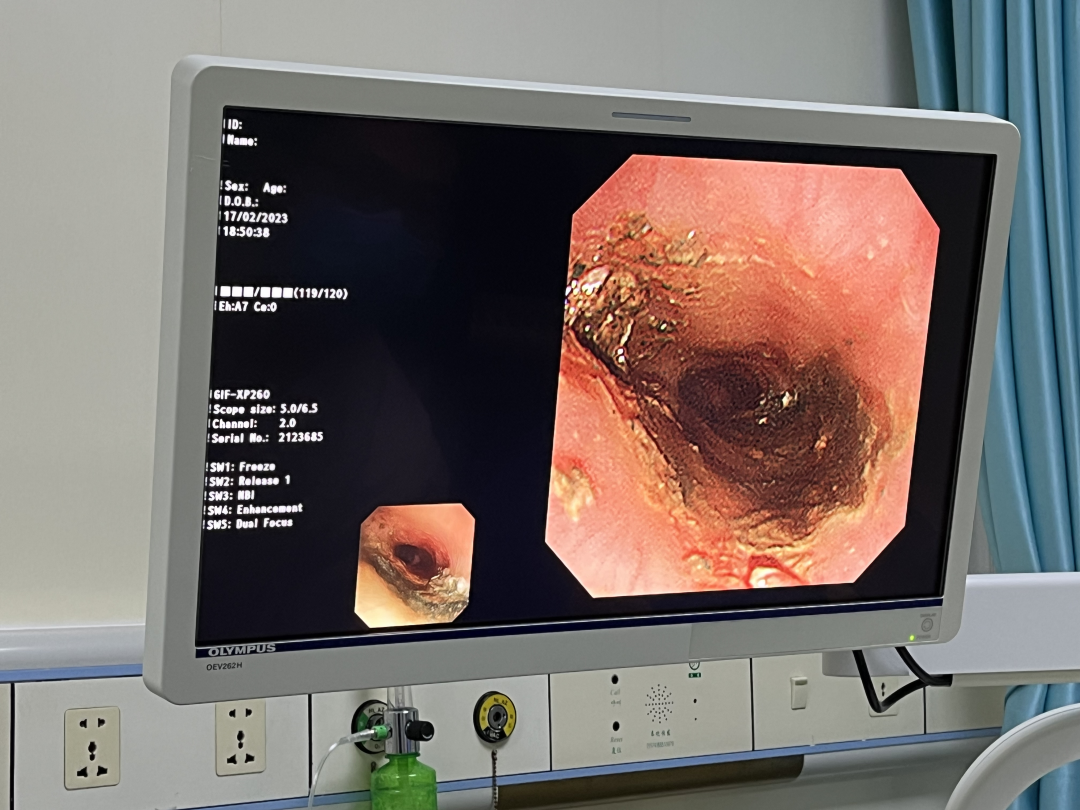

时间就是生命,每提前争取1分钟,就可减少纽扣电池对患儿的损伤。郝医生在谈话间迅速与患儿家属沟通,告知其风险性、利害关系后,快速跑入内镜室,紧张的救治即刻开始。患儿胸部X线片提示纽扣电池位于食管上段狭窄处,10个月大的患儿不同于成年人,操作空间有限,加大了操作难度,儿内二科、麻醉科医生护士争分夺秒,在患儿全身麻醉下,采用无痛电子胃镜联合异物钳,顺利取出一枚直径1.5厘米的圆形纽扣电池。

图片

警报虽然解除,但术中发现患儿食管粘膜后壁侧发黑、质脆,取出后可见患儿食管上段距门齿约12-16cm处后壁大范围电灼伤。郝医生考虑到,可能由于患儿呕吐导致电池短路引起食管损伤,可能出现感染、食管穿孔、水肿压迫气管影响呼吸、出血、食管气管漏等近期并发症,可能出现食管狭窄、吞咽困难等远期并发症。给予留置胃管,少量多次喂养,嘱咐患儿头高脚低体位,避免返流对症治疗。